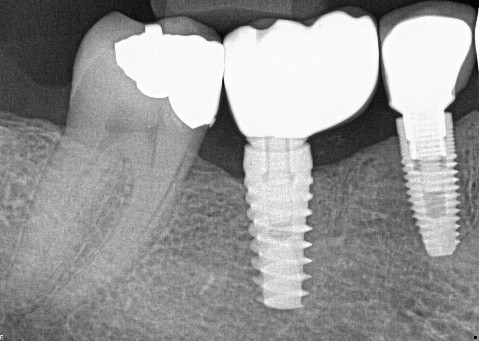

There is radiographic evidence of

Regarding tooth 4.6, there is evidence of